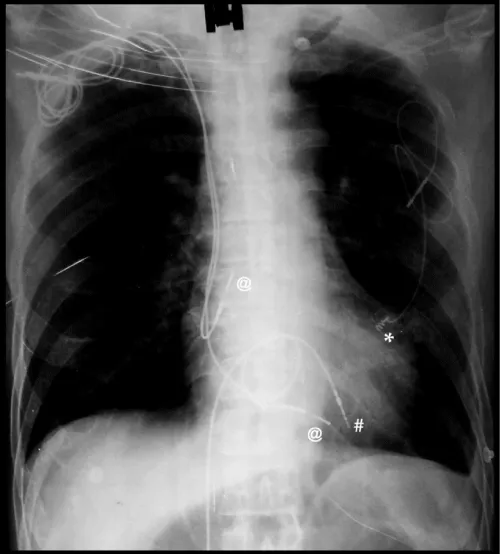

Due to exhaustion of other options, alternative access option was warranted. Therefore, pacemaker implantation via right external iliac vein (EIV) was considered. Under aseptic conditions and local anesthesia, a guidewire was placed in right common iliac vein by puncturing right femoral vein. With fluoroscopic guidance, right EIV was punctured 4 cm above midpoint of inguinal ligament after making an incision and dissecting upto fascial plane, with a 16-gauge needle taking care to avoid arterial puncture (Figure 2). Using a 16 cm peel away sheath, a long RV active fixation lead (Lead 5076, 85 cm, Medtronic) was screwed in RV apex after satisfactory pacemaker parameters were achieved. An alpha loop was made in right atrium to reduce risk of dislodgement (Figure 3). An inverted L-shaped dissection was done around puncture site and lead was doubly secured to external oblique fascia, at the puncture point, and, after making a U-turn superiorly using an additional suture sleeve (Figure 2, schematic). Lead was then tunneled subcutaneouly to the pacemaker pocket created by a separate incision over right lumbar region above external oblique fascia. A VVIR (RESR01-RELIA, Medtronic) pulse generator was also doubly secured to underlying fascia and subcutaneous tissue to prevent gravitational sagging. Finally, tissue and skin were sutured in layers and pressure dressing was done. Operating time was 78 minutes. Abdomino-thoracic radiograph showing final position of old leads and new implant is seen in figure 4.

Figure 3: (Final position of pacemaker, new transiliac ventricular lead (#), old subclavian atrial (@) & ventricular leads (@), and epicardial lead (*) on thoracic-abdominal radiograph.

Figure 4: Abdomino-thoracic radiograph showing final position of old leads and new implant.